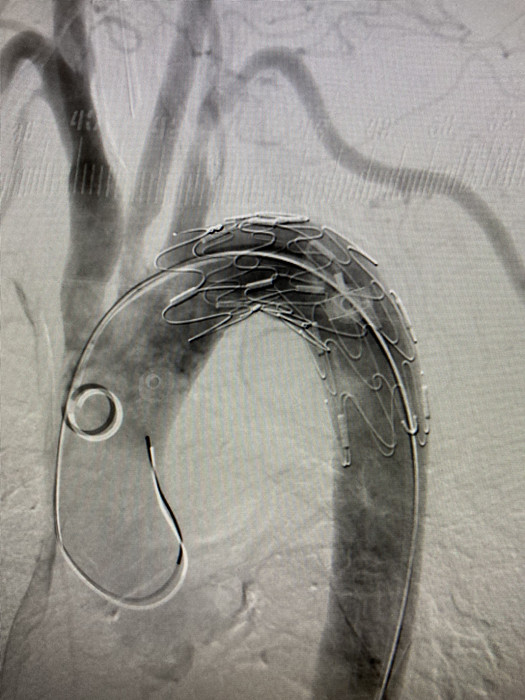

凌晨4點,血管外科副主任醫(yī)師程國兵,主治醫(yī)師李曉陽,為劉奶奶進(jìn)行了胸主動脈支架植入手術(shù),歷經(jīng)1小時,手術(shù)順利結(jié)束。

隨后,消化內(nèi)科副主任醫(yī)師趙黎明在內(nèi)鏡下探查另一處“隱患”,小心翼翼夾準(zhǔn)另一塊鴨骨邊緣慢慢拖出,“取出來了!”經(jīng)內(nèi)鏡中心醫(yī)護(hù)人員的默契配合,鴨骨終于從食管中取出。一大塊鴨肉夾雜著兩塊尖尖的鴨骨頭,其中長的鴨骨頭長約4cm。